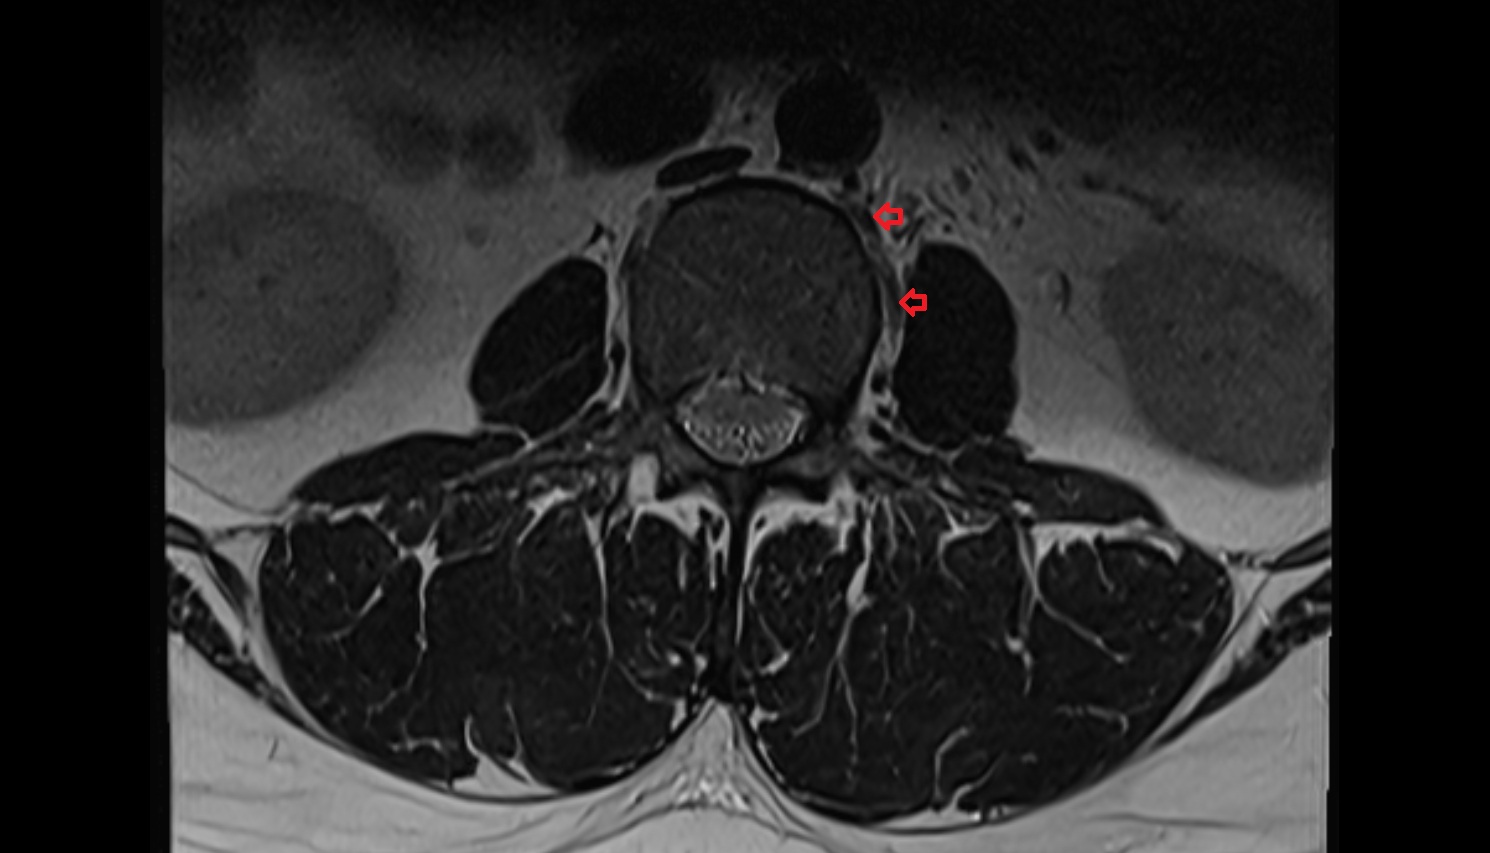

- Traversing nerve root of spinal nerve

- Exiting nerve root of spinal nerve

- Dorsal traversing nerve root

- Ventral traversing nerve root

- Dorsal exiting nerve root

- Ventral exiting nerve root